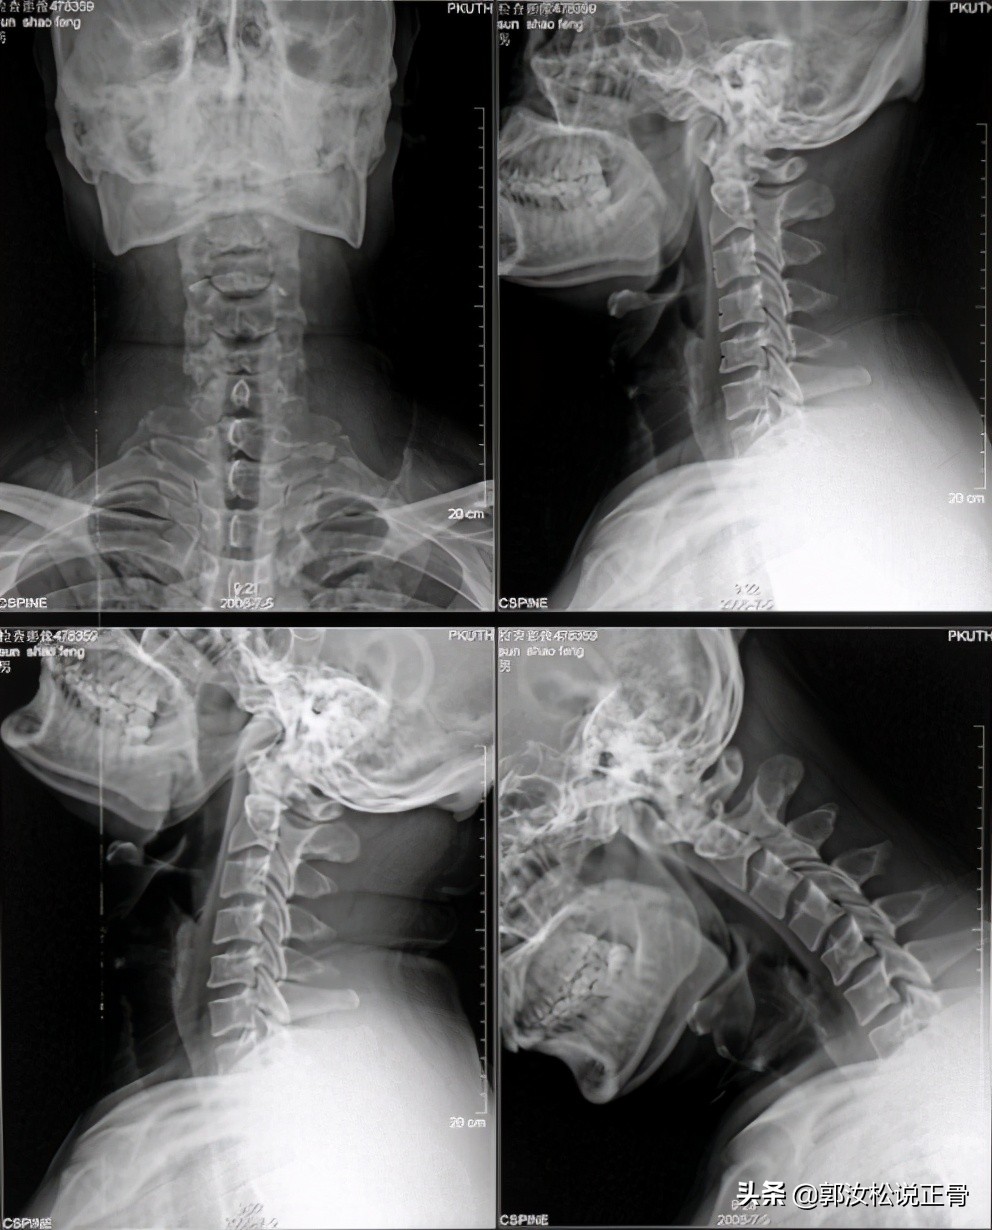

X光检查提示: 颈椎生理曲度变直,轻度骨质增生。

// 诊断:颈源性头痛 //X光检查: